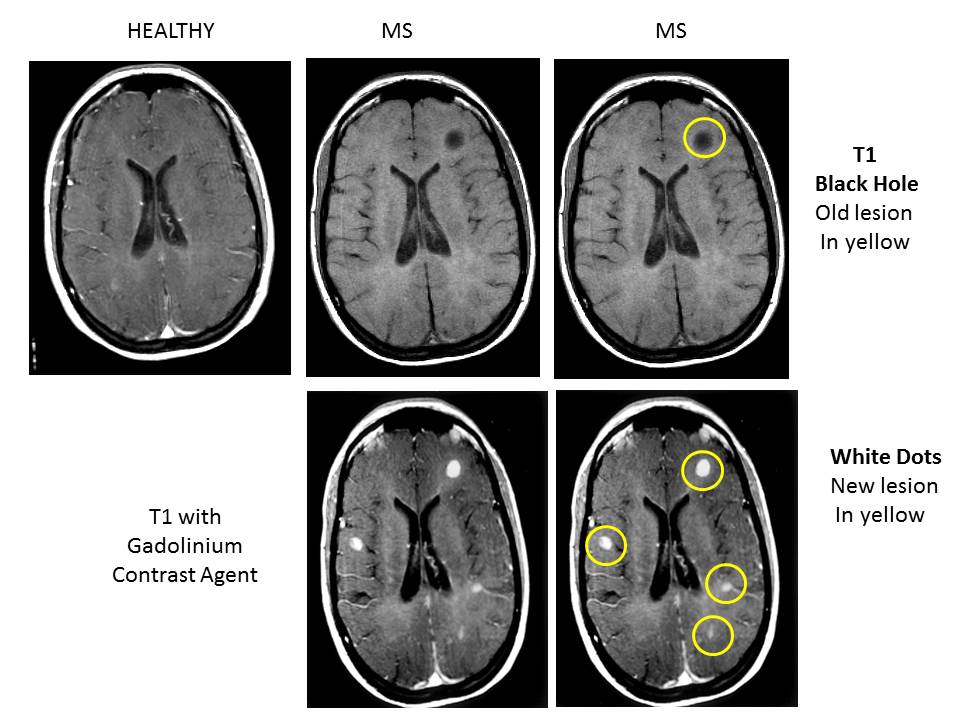

How Does Ms Appear On Mri . Doctors use mri scans to look for lesions. The gadolinium shows up white. An mri uses magnetic fields and radiofrequency to measure water content in the body's tissues. Learn about the uses and. The majority of people with ms have abnormal mri imaging. Doctors may also use a type of scan called flair,. Since the myelin that protects. What does ms look like on an mri? In ms they often use an mri scan with contrast. Magnetic resonance imaging (mri) is a common tool for diagnosing ms. What does multiple sclerosis look like on an mri? An mri shows the spinal cord and brain in many different positions. Doctors may find most spinal cord lesions in people with ms. This means they inject a contrast fluid that contains gadolinium. Magnetic resonance imaging (mri) plays a crucial role in multiple sclerosis (ms) diagnosis, disease monitoring, prognostication, and research.

Doctors may find most spinal cord lesions in people with ms. The gadolinium shows up white. Since the myelin that protects. What does ms look like on an mri? The majority of people with ms have abnormal mri imaging. In ms they often use an mri scan with contrast. An mri uses magnetic fields and radiofrequency to measure water content in the body's tissues. Magnetic resonance imaging (mri) is a common tool for diagnosing ms. Doctors use mri scans to look for lesions. Magnetic resonance imaging (mri) plays a crucial role in multiple sclerosis (ms) diagnosis, disease monitoring, prognostication, and research.

How Does Ms Appear On Mri Doctors may find most spinal cord lesions in people with ms. What does multiple sclerosis look like on an mri? An mri shows the spinal cord and brain in many different positions. Doctors may find most spinal cord lesions in people with ms. The gadolinium shows up white. Doctors use mri scans to look for lesions. The majority of people with ms have abnormal mri imaging. This means they inject a contrast fluid that contains gadolinium. Magnetic resonance imaging (mri) is a common tool for diagnosing ms. Magnetic resonance imaging (mri) plays a crucial role in multiple sclerosis (ms) diagnosis, disease monitoring, prognostication, and research. An mri uses magnetic fields and radiofrequency to measure water content in the body's tissues. Learn about the uses and. Doctors may also use a type of scan called flair,. Since the myelin that protects. What does ms look like on an mri? In ms they often use an mri scan with contrast.